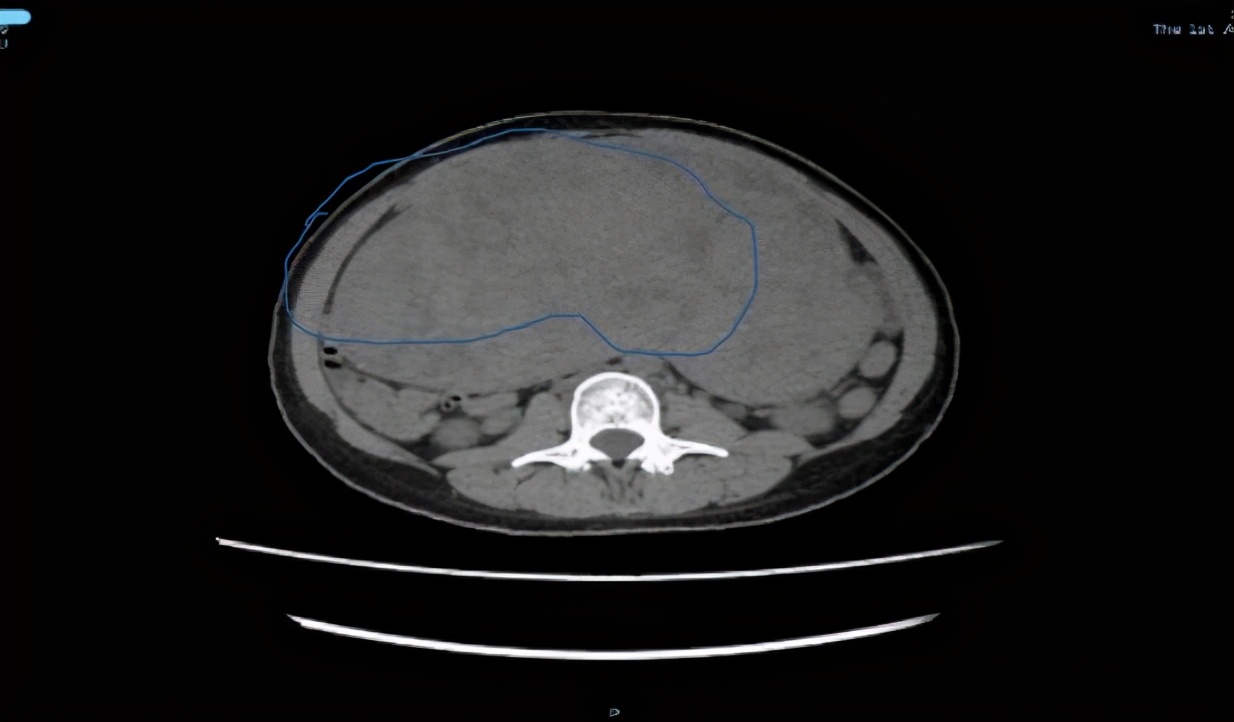

“未见其人,先见其腹”!体重50公斤的黄女士来暨南大学附属第一医院就诊时,她的肚子却巨大得异常突兀,经过全腹CT检查,结果显示:腹盆腔内见一巨大软组织肿块影,大小约22cm*10cm*28cm。子宫后发盆腹腔探及一实性光团,考虑盆腹腔巨大实性占位病变。抽血检查显示,包括肿瘤标记物均正常。

术前CT检查 腹腔内巨大肿物